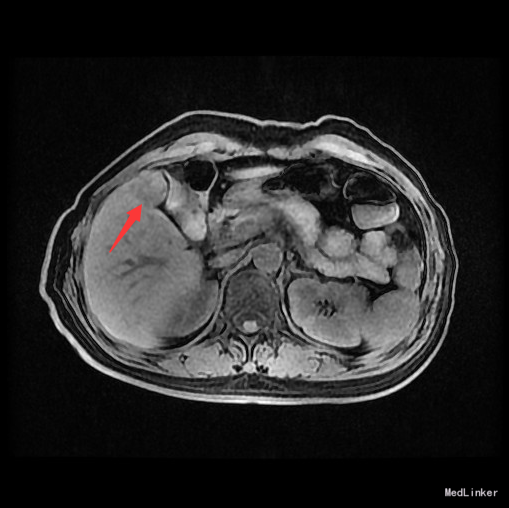

查体:腹平,腹壁静脉无显露,腹软,无压痛,无反跳痛。肝肋下未及。 辅查:AFP 3.43ng/ml, CEA 1.47ng/ml。MR:肝S5段占位性病变(26*25mm),考虑肝癌可能性大,建议活检。

随访:术后病理示:(右肝肿物)送检肝组织部分呈结节状增生,结节间见粗细不等的纤维间隔,其内见血管增生,少量淋巴细胞及浆细胞浸润,符合肝局灶性结节状增生(FNH)。 讨论:肝局灶性结节增生(FNH)是肝内第二常见良性肿瘤,一般无临床症状,影像学表现,MRI上T1WI和T2WI与周围肝实质信号相近,增强扫描动脉期明显强化,若存在中央瘢痕,则中央瘢痕不强化,门脉期及静脉期强化程度减退,中央瘢痕则呈延迟强化。FNH需与肝癌和肝腺瘤鉴别,本例即误诊为肝癌,若存在中央瘢痕,则诊断较容易。